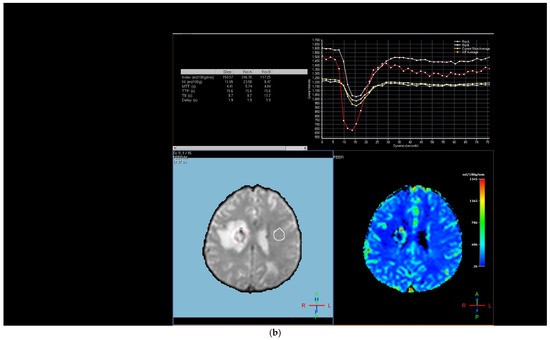

Figure 2. Brain magnetic resonance imaging (MRI) of a 67-year-old male with small-cell lung carcinoma revealed (a) peripherally enhanced right periventricular mass on post-contrast axial T1-weighted image and (b) hyperperfusion with a rCBV of 2.4 in perfusion-weighted imaging. Pink ROI is from metastatic nodule and white ROI is from contralateral parenchyma.